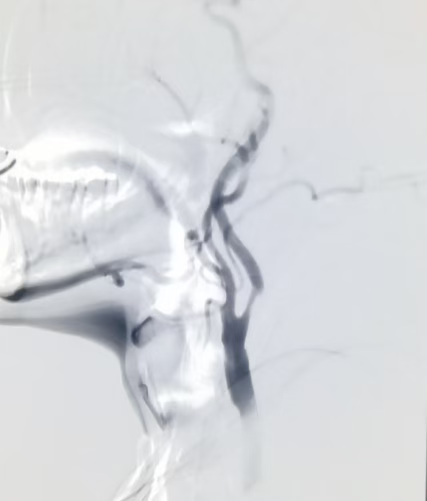

术前DSA示颈动脉重度狭窄

术后DSA见颈内动脉显影清晰,血流灌注良好